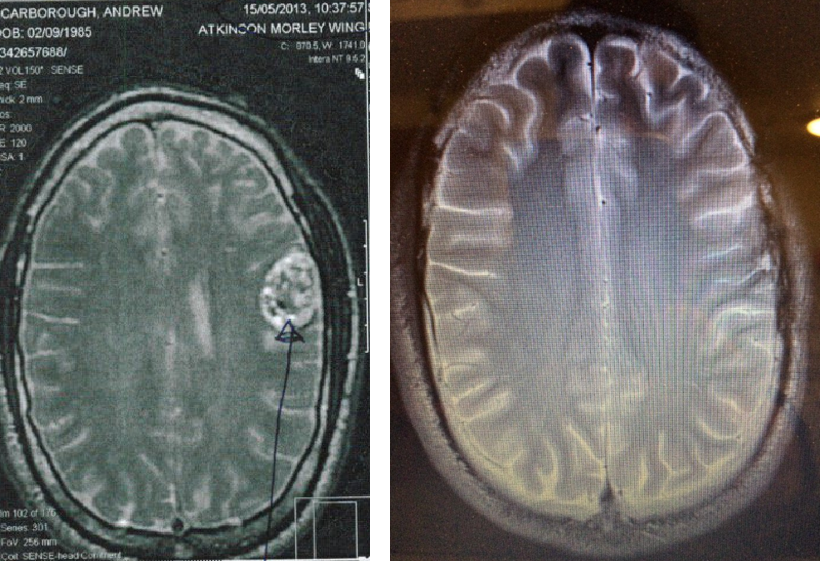

Slowly Andrew noted improvements in energy, headaches and seizure frequency. He found an amazing group of supportive doctors including Dr. Kevin O’Neill at the Charing Cross Hospital, Imperial College London where he lives. Andrew was able to stop all of his anti-seizure medication and at two years from diagnosis his doctors agreed that his tumor appeared to be in remission. His most recent scans now at two and a half years from diagnosis again demonstrate remission with a small area of remnant scar tissue.

Initial Scan (L) 05/15/2013 Tumor/Hemorrhage – Most Recent Scan (R) 11/02/2015 Remnant Scar Tissue